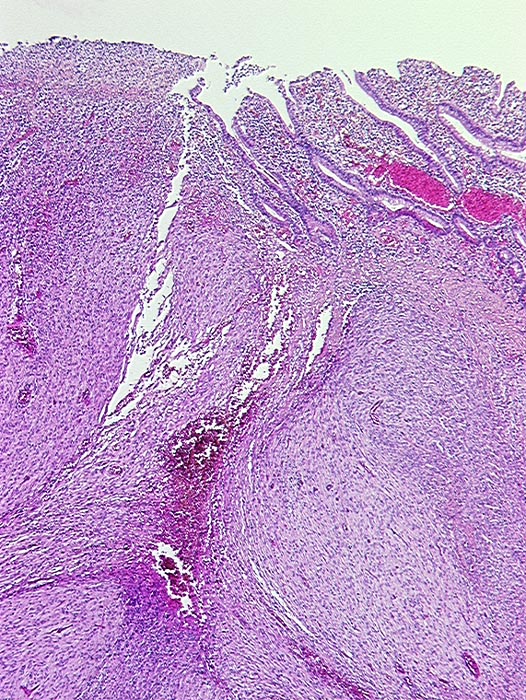

• Über dem Tumor entzündungsfreie Antrumschleimhaut mit partiell reepithelialisiertem oberflächlichem Ulkus (Quellungsfibrinoid).

• Der Tumor besteht aus längs und quer getroffenen Faszikeln spindelförmiger Tumorzellen, welche an glatte Muskelzellen oder Schwannzellen erinnern.

• Herdförmig pseudozystische Auflockerung des Tumorgewebes.